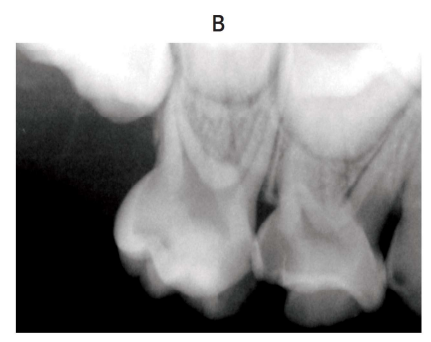

4 歳の女児。上顎右側乳臼歯部の激しい疼痛を主訴として来院した。 3 か月前に上顎右側D のコンポジットレジンの脱離に気付いていたが、症状がないためそのままにしていたところ、昨晩から痛みが続いているという。上顎右側のD に打診痛を認める。初診時の口腔内写真(別冊No. 21A)とエックス線画像(別冊No. 21B)を別に示す。

解答:c

解説:

根尖病巣はなさそう。

打診痛あり、痛みもある⇒歯髄まだ生きてそう。後継歯の歯冠もしっかりできているので⇒抜髄

抜歯してしまうと、4がはえてくるのはまだ先なのでスペースが空いてしまうので残しておくのがよい。